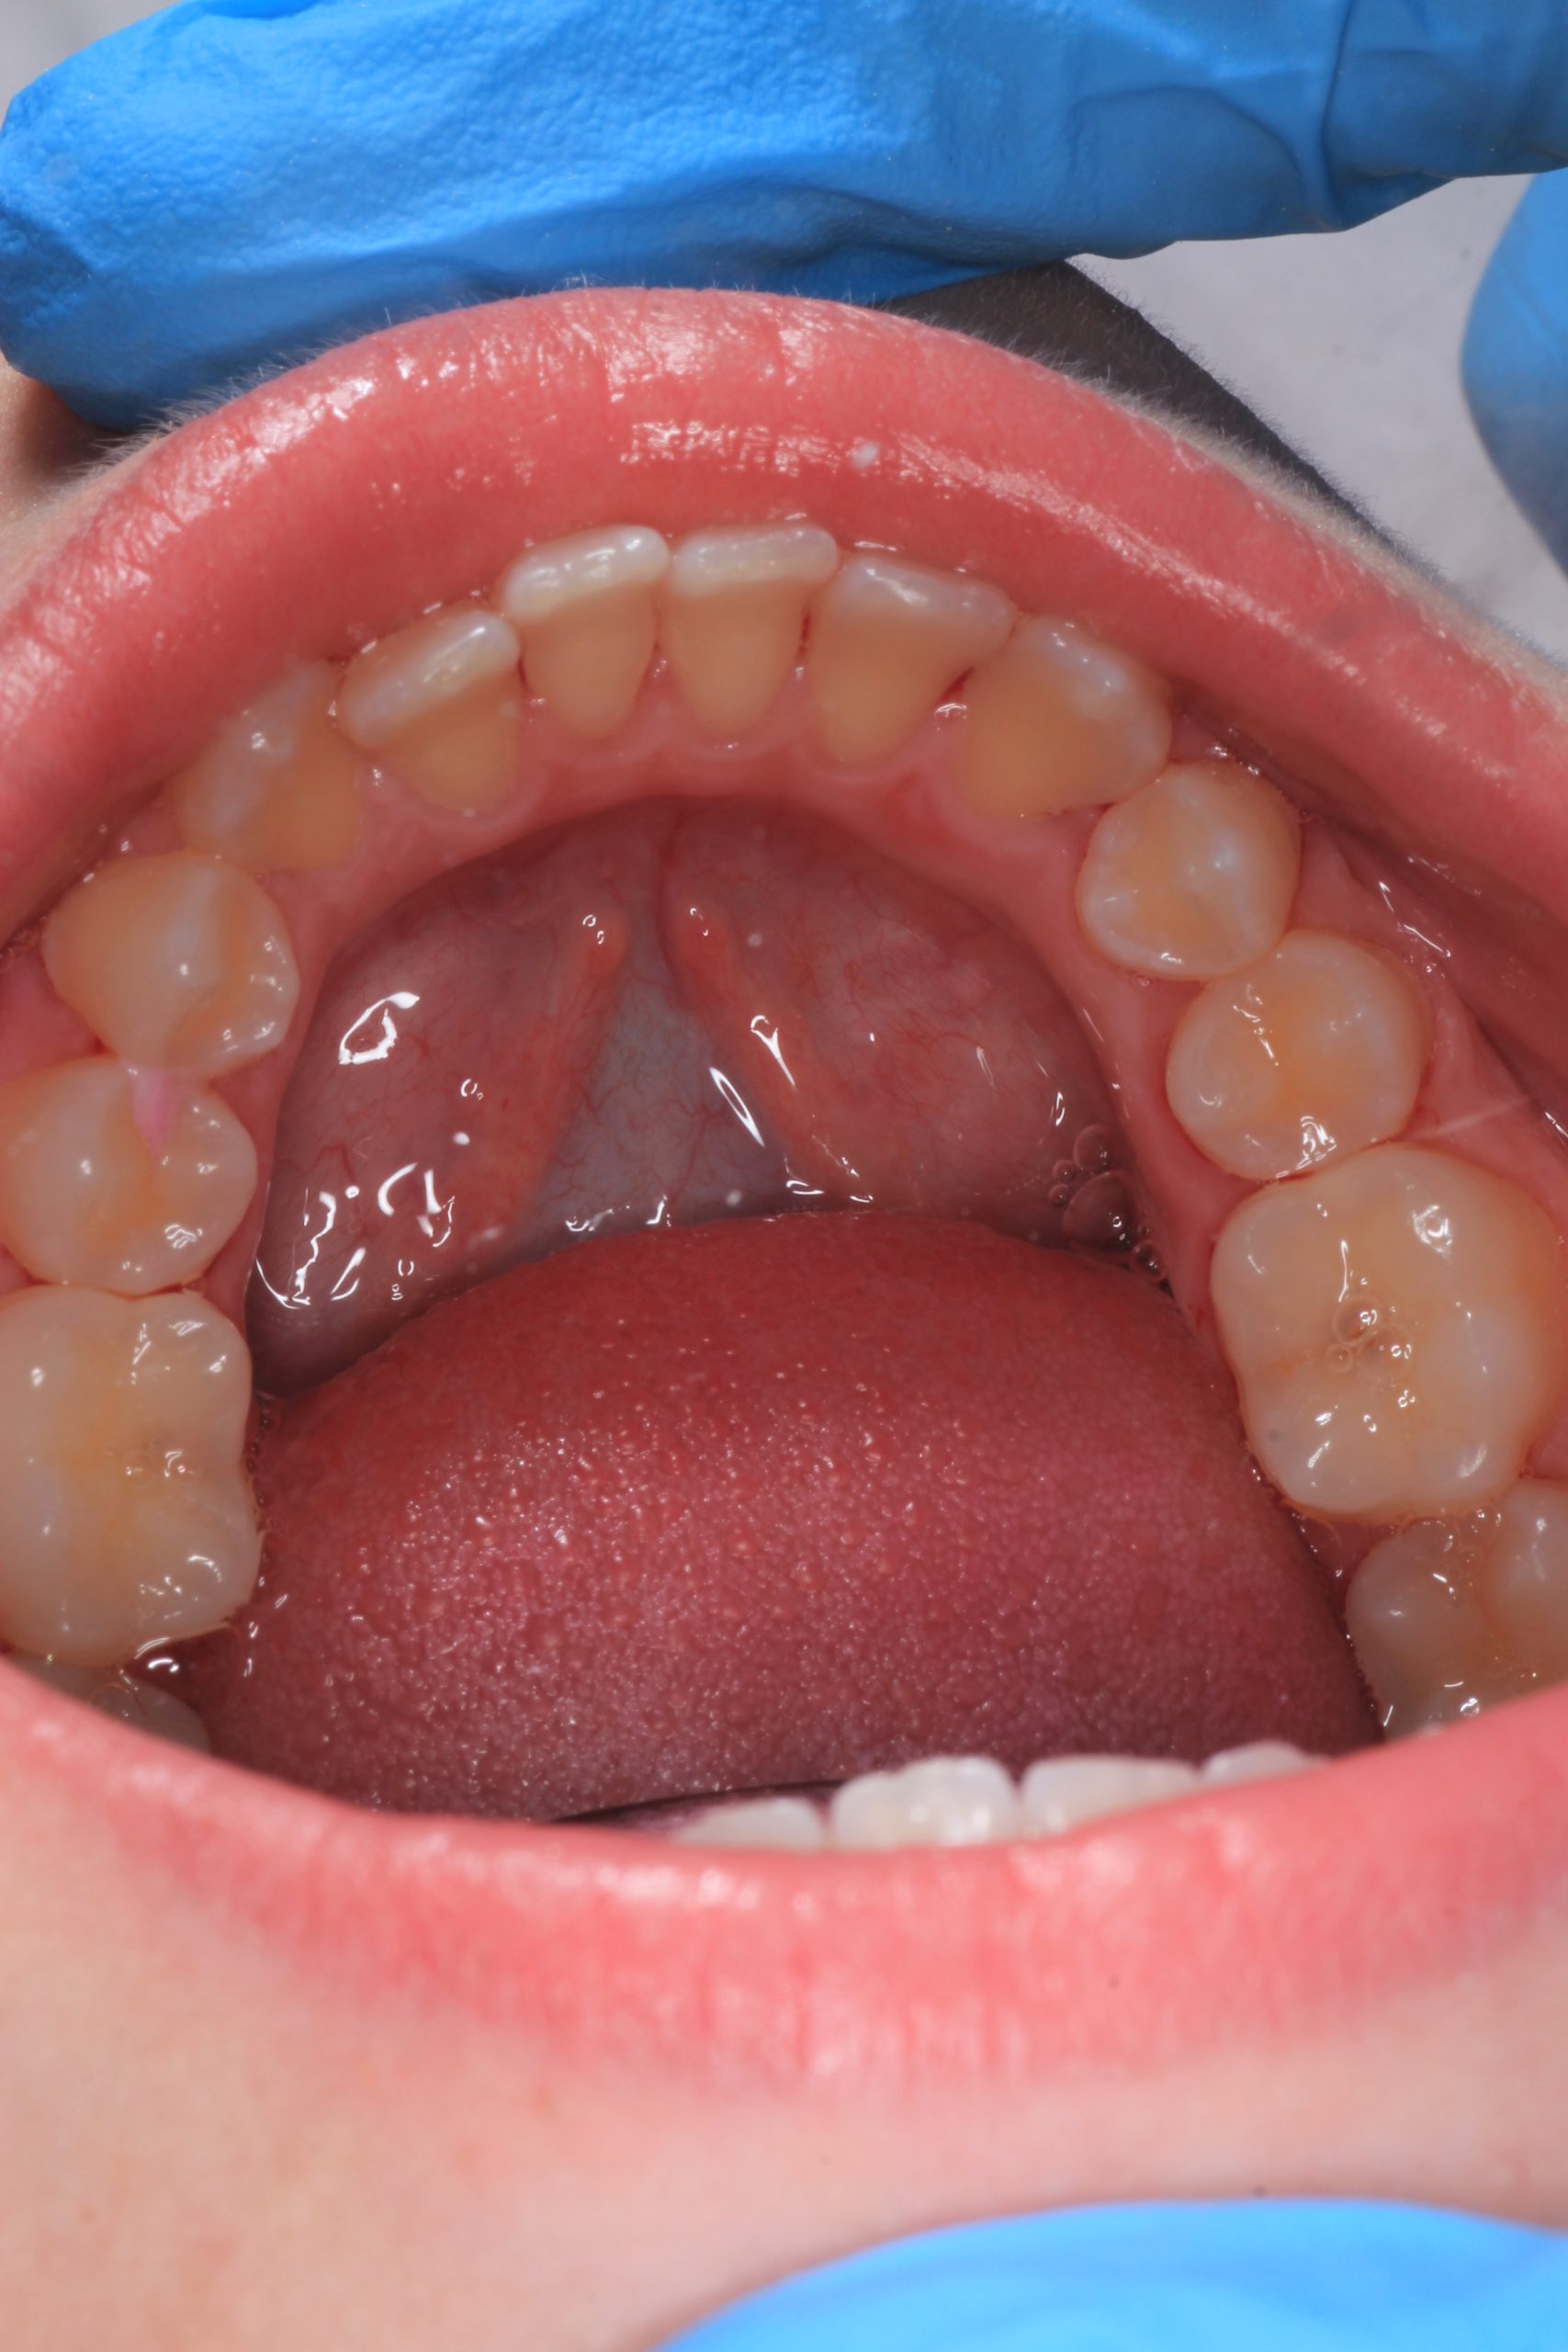

We examine the condition of teeth, gums, and bite. - Plaque Disclosure with Special Indicators

Areas that weren’t cleaned well appear purple. The darker the shade, the older the plaque. This helps both kids and parents understand where brushing needs to improve. - Brushing Training & Home Care Tools Selection